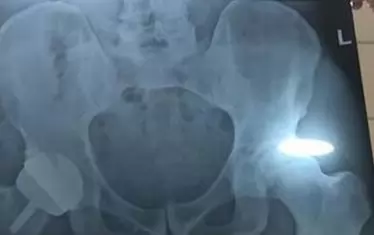

Днес Мъри написа в "Туитър: "Имам метална става. Чувствам се малко поочукан и наранен, но се надявам, че това ще е краят на болките ми в хълбока". Той публикува и рентгенова снимка на новата си става. Тенисистът бе записан за турнира в Марсилия (Фр) през февруари, но още в петък е е оттеглил заявката си.